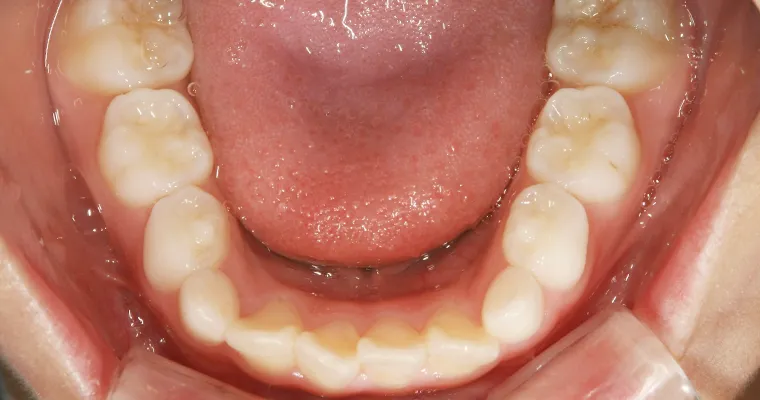

下顎咬合面観

BEFORE

AFTER